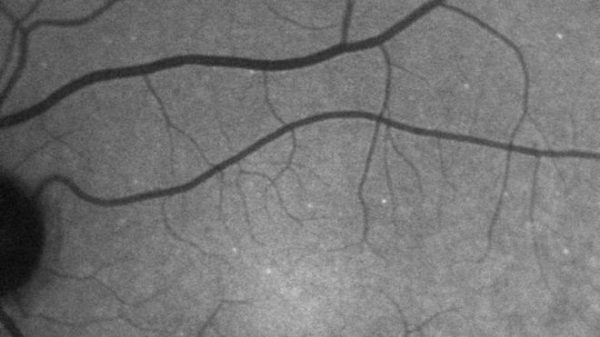

ويستخدم الاختبار صبغة فلورية تلتصق بالخلايا التي أشرفت على الموت داخل الشبكية.

وبينما تتعرض تلك الخلايا للضغط وتصبح أكثر ضعفا، تبدأ في تغيير تركيبتها الكيميائية ما يؤدي إلى تحرك هياكل أكثر دهنية خارج الخلية.

وهذا هو الجزء الذي تلتصق به الصبغة الفلورية التي تُحقن في مجرى الدم.